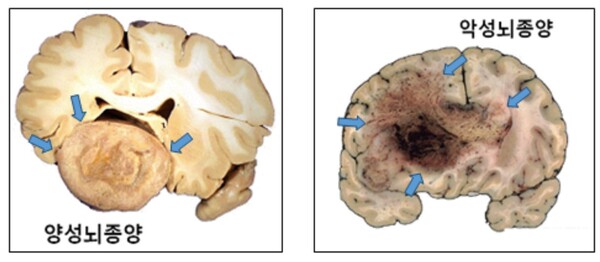

![[자료4] 악성 뇌종양(교모세포종) MRI](https://cdn.healthlifeherald.com/news/photo/202507/2798_4817_1052.jpg)

진단과 치료, 무엇이 중요한가?

뇌종양 진단에는 MRI가 핵심적인 역할을 하며, 수술을 통해 종양 조직을 채취해 조직 검사와 유전자 검사를 병행해야 최종 진단이 가능하다.